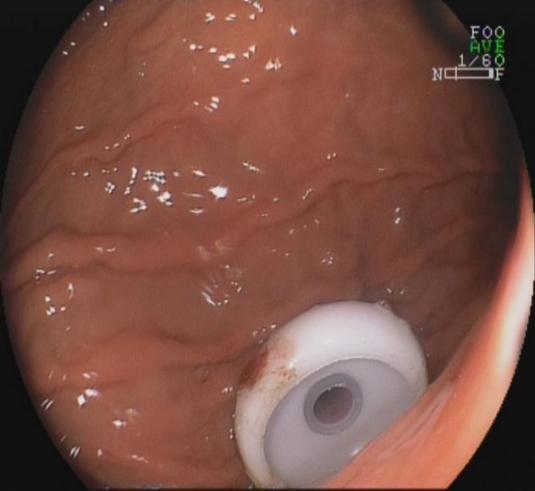

六、内镜下经皮胃造瘘术

内镜下经皮胃造瘘术是一种通过胃镜介导放置胃造瘘管进行肠内营养或胃肠减压的方法,与传统的外科胃肠造瘘术相比,内镜下经皮胃造瘘术无需全身麻醉和外科手术,操作相对简便,术后并发症少,在临床上得到迅速广泛应用。尤其是对于不能长期经口进食的患者和神经系统疾病的危重症患者,应用内镜下经皮胃造瘘术给予肠内营养具有独特的优势,可迅速恢复患者的胃肠功能,减少吸入性肺炎的发生,有效的延长生命。我科是广西区内开展内镜下经皮胃造瘘最早的科室,在治疗上有十分丰富的经验。

胃造瘘胃体内一端